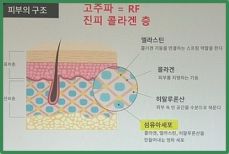

프로테오글리칸은 피부의 수분을 유지하고 탄력을 강화하는 데 중요한 역할을 합니다. 피부 세포 간의 수분 보유력을 높여주어 건조함을 예방하고, 피부의 유연성을 증가시켜 주름과 처짐을 방지합니다. 이는 특히 노화로 인한 피부 변화를 완화하는 데 효과적입니다. 프로테오글리칸은 피부의 진피층에서 콜라겐과 엘라스틴의 구조를 지지하며, 피부의 전반적인 건강을 향상시킵니다. 피부 장벽을 강화하여 외부 자극으로부터 피부를 보호하고, 손상된 피부의 재생을 촉진합니다. 이를 통해 피부가 더욱 건강하고 생기있게 유지될 수 있습니다.